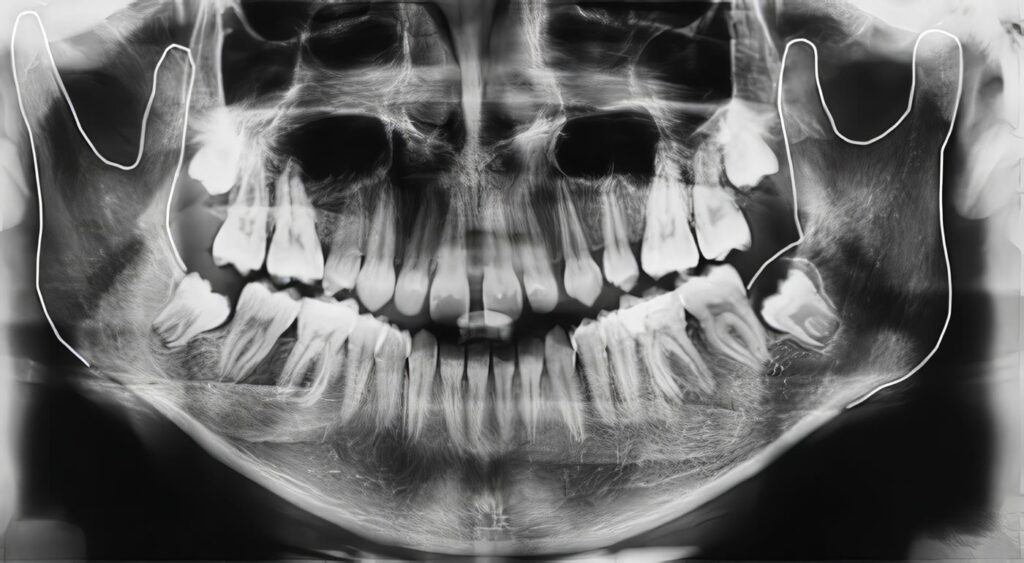

Quistes Ontogénicos en Maxilar Inferior

Reporte de tres casos Dr. JUAN MANUEL CHIRIBY* Dra. DORIS BALLESTEROS** * Jefe Servicio Cirugía Oral y Maxilofacial. Hospital Central...